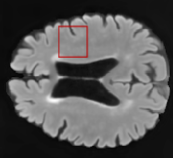

Table 2: Segmentation results for all proposed methods, each column represent a different slide in the image, blue areas are regions which were correctly labeled, false positives are shown in green, and false negatives in yellow

In order to better understand the above results, we visually analyzed the output segmentation performed for each method. Table 2 shows the results for three different slices (one slice per column). As illustrated, the proposed method is able to produce less false positives. It is also important to note that, unimodal segmentation is the one that produces more false positives, showing the advantage of using synthetic data. Regarding the nature of false positives, it can be easy to see in the third column a large number of false positives are on the border of periventricular lesions for the Unimodal method in comparison to the proposed method. Also from the first and second column, it can be observed that Unimodal tend to produce more small regions of false positives near to cortical areas. Removing such false positives requires additional post-processing steps, therefore, it is of value avoid this kind of over-segmentation. It can also be noted that synthesis methods tend to produce the same kind of false negatives, this may be due to the blurring effects in synthesized images since the information available during testing is limited – which otherwise is available from a FLAIR sequence.